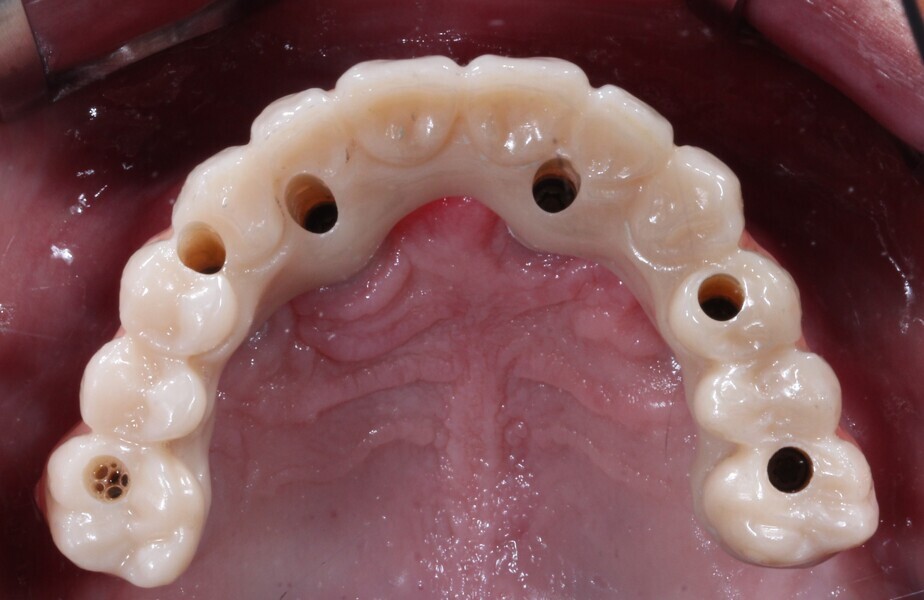

Fig. 21: Final maxillary prosthesis, occlusal view.